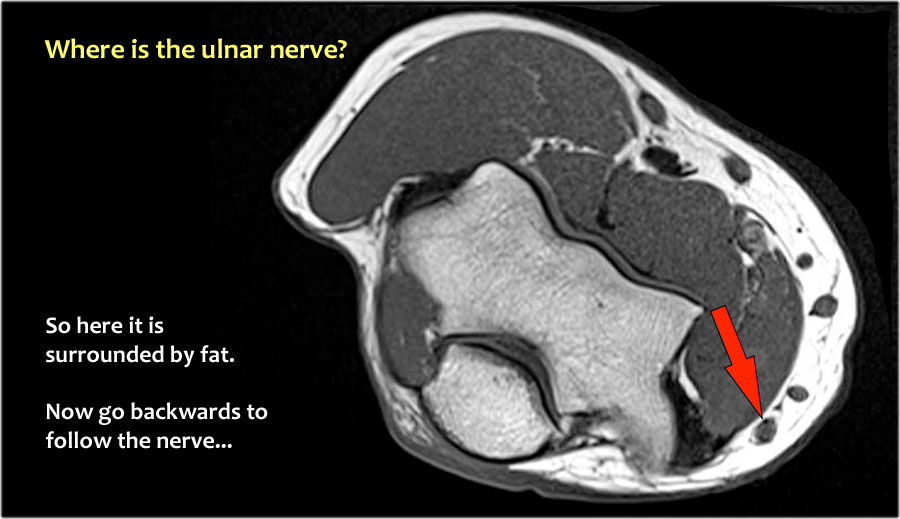

Một cách để thực hiện là đi theo các cấu trúc về phía xa cho đến khi tìm thấy dây thần kinh trụ ở phía xa tại vị trí bình thường của nó ở vùng cẳng tay gần được bao quanh bởi mô mỡ.

Sau đó khi bạn theo dõi nó về phía gần, bạn sẽ nhận thấy rằng đây là một trường hợp chuyển vị dưới da.